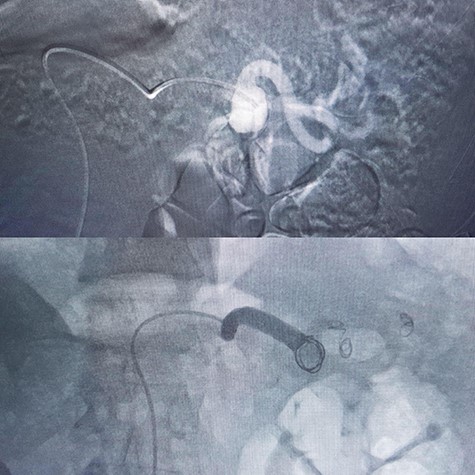

In a 52-year-old man (third patient), 3-cm SAA was found incidentally in ultrasound and CTA. According to size of the aneurysm, he was candidate for endovascular treatment. Angiography and positioning of the coils on either side of the aneurysm (‘sandwich technique’) was completed (Fig. 3). Post-embolization checks were performed with selective splenic, celiac and superior mesenteric artery angiograms to confirm occlusion of the main splenic artery and patency of the collateral arteries. All seven patients discharged with no procedure-related complications.

There are two embolization techniques: endovascular ligation that requires the positioning of the coils on either side of the aneurysm (‘sandwich technique’) to attain complete occlusion. For patients with large or multiple SAAs, total embolization of the splenic artery must be performed to produce complete occlusion of the SAAs [9]. In cases 4 and 5 we started EVT but as they were giant aneurysms we continued by laparotomy (the hybrid surgery).